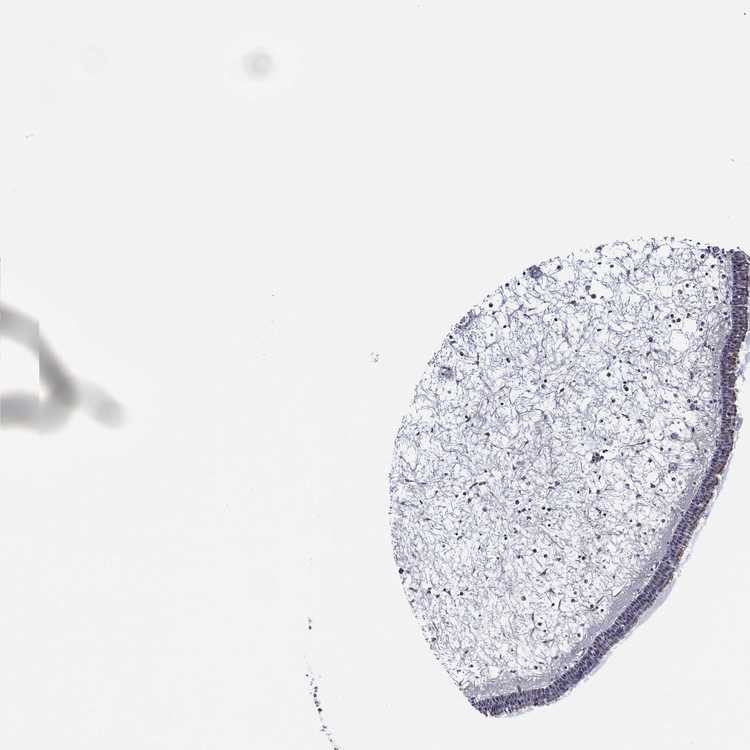

NASOPHARYNX - Antibody stainingi

Antibody staining in the annotated cell types in the current human tissue is reported as not detected, low, medium, or high, based on conventional immunohistochemistry profiling in selected tissues. This score is based on the combination of the staining intensity and fraction of stained cells.

Each image is clickable and will lead to virtual microscopy that enables deeper exploration of all samples and also displays staining intensity scores, fraction scores and subcellular localization as well as patient and tissue information for each sample.

Antibody HPA008057

Respiratory epithelial cells Low